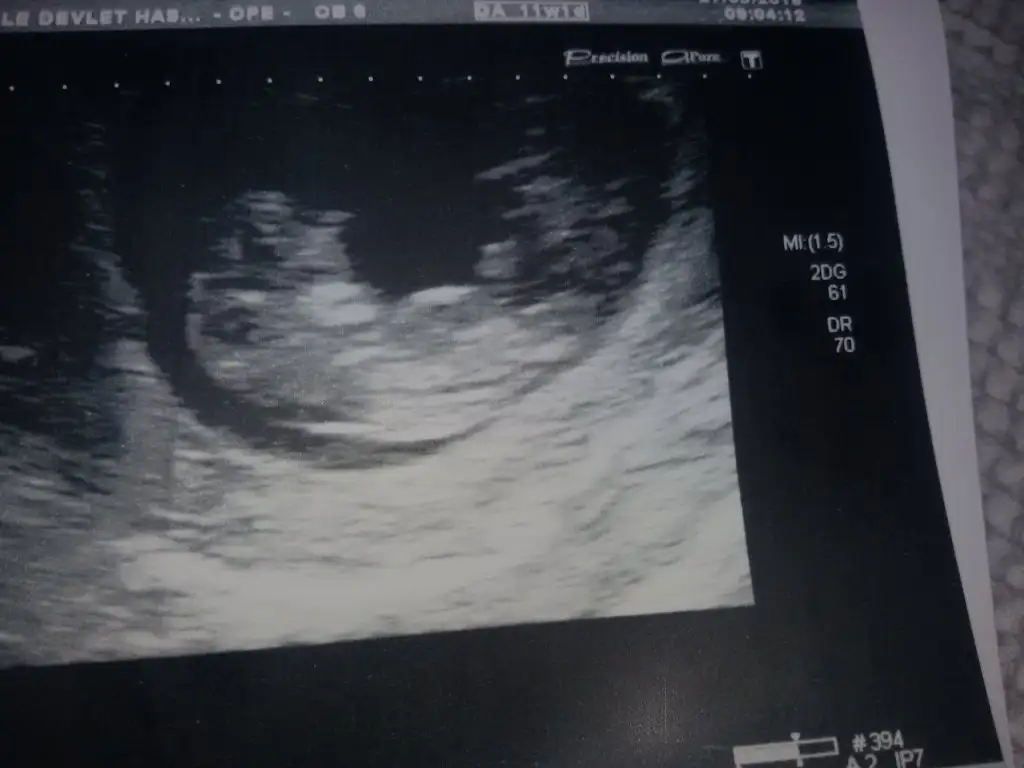

Merhaba arkadaşlar.. Herkes sağlıkla alsın inşallah bebişini kucağına.. 7. Haftadayım bende. 6+3 fotosuna göre sizce neye benziyor :)

Eklentiler

• image.webp

image.webp

19,2 KB · Görüntüleme: 171

güya kese fasulyeye benzıyorsa erkek olurmus rivayetlere göre

bebişe gelırsek cok net bır sekılde sağda kamp kurmus :D

kesenın şekline göre erkek

bebişin yerıne göre kız :D